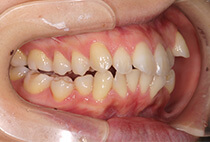

治療前